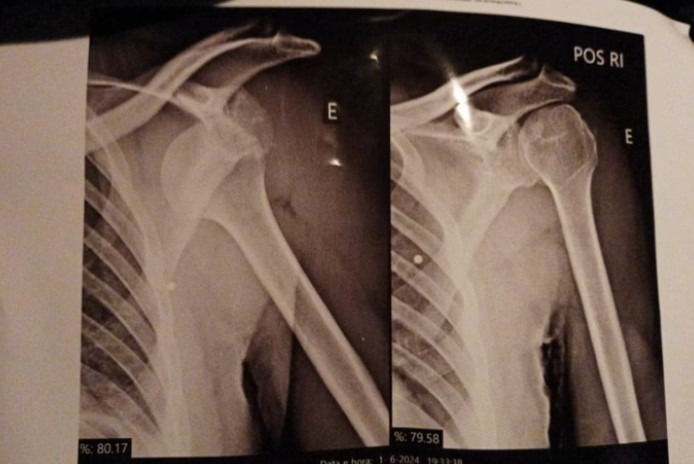

Outro ponto denunciado por Lucas é a dificuldade de atendimento no Hospital da Polícia Militar (HPM). Ele sofreu duas luxações nos ombros, foi socorrido por viaturas da própria PM, mas precisou esperar horas por atendimento, sem conseguir consulta com ortopedista.

Lucas relata que hoje até tarefas simples, como vestir uma camisa, se tornaram um desafio. O ombro esquerdo já foi operado, mas ele ainda sente dores e precisa de fisioterapia. O direito também deverá passar por cirurgia.